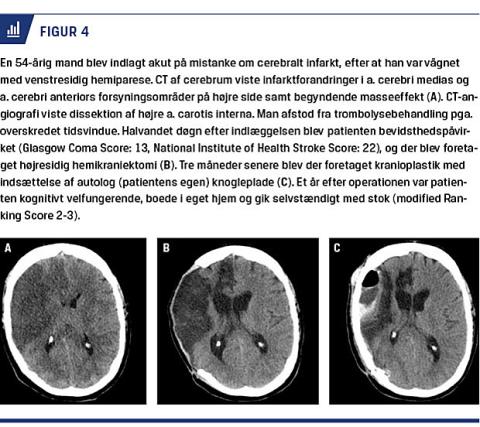

timer efter symptomdebut, og viste ved kirurgisk behandling en signifikant reduktion i mortaliteten inden for 12 måneder fra 71% til 22% (absolut risikoreduktion (ARR) 50,3% (95% KI: 33,3-67,4%); p < 0,0001) [22]. I analysen er funktionelt outcome dikotomiseret til modified Ranking Score (mRS) 0-4 (kaldt favourable) vs. mRS 5-6 (kaldt unfavourable) efter 12 måneder (Figur 3). Andelen af patienter, som havde mRS > 4 efter et MMI, dvs. som enten var svært plejekrævende eller døde, blev ved kirurgisk behandling reduceret fra 76% til 26% (ARR 51,2% [95% KI: 33,9-68,5%]; p < 0,0001), svarende til number needed to treat på kun to for overlevelse med mRS ≤ 4. Effekten af hemikraniektomi på funktionelt outcome er genfundet i et Cochranereview fra 2012, hvor alle patienter fra HAMLET-studiet, inkl. patienter, som blev opereret 48-96 timer efter symptomdebut, er inkluderet (OR: 3,85 for mRS ≤ 4 ved hemikraniektomi vs. medicinsk behandling [95% KI: 1,96-7,69], p < 0,0001) [24] (Figur 4 beskriver en illustrativ sygehistorie). Outcome hos patienter > 60 år er senest undersøgt i DESTINY II, og også her viste kirurgisk behandling en gavnlig effekt på især mortaliteten, men også på funktionelt outcome, idet 38% vs. 18% af patienterne opnåede en mRS ≤ 4 efter seks måneder (OR: 2,91 for mRS ≤ 4 (95% KI: 1,06-7,49); p = 0,04). [23]. Dog opnåede størstedelen af patienterne med favourable outcome i denne aldersgruppe kun mRS 4, og operationsindikationen beror derfor i praksis på en grundig vurdering af evt. komorbiditet, der kan komplicere efterforløbet.